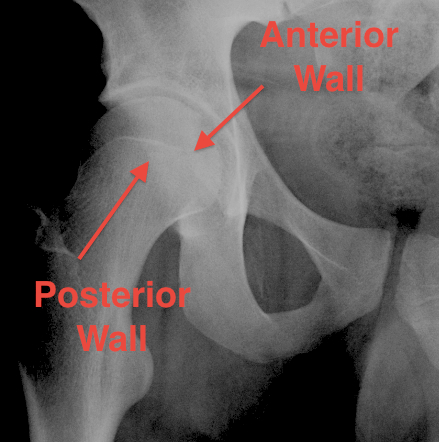

6. Post rim of acetabulum

Judet views / 45o obliques

Internal Oblique / Obturator Oblique

- affected side rotated forward

- anterior column + posterior wall

External Oblique / Iliac Oblique

- unaffected side rotated forward

- posterior column + anterior wall